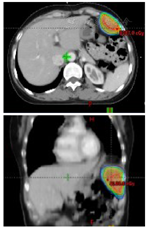

入院后于2019年10月11日行彩超引导下左上腹壁包块穿刺活检术。术后病理示:(左上腹腹壁)肿瘤细胞呈圆形,卵圆形。免疫组化:(左上腹腹壁)肿瘤细胞TDT(+),CD5(+),CKpan(+),Ki-67(+,约30%),p53(+,约10%),CD56(-),CgA(-),Syn(-),CD20(-)。结合HE切片及病史,考虑为胸腺瘤转移(图1B)。患者及家属拒绝手术治疗及化疗,于2019年10月23日起予以左上腹壁转移灶姑息放疗(图2),GTV为影像学所示左侧腹壁转移灶,PGTV为GTV外放0.5 cm。第1阶段:GTV 3.0 Gy/次,共16次;PGTV 2.0 Gy/次,共16次;二次定位提示腹壁转移灶较前明显退缩(图4B),予以缩野加量。第2阶段:PGTV-new:2.0 Gy/次,共10次。